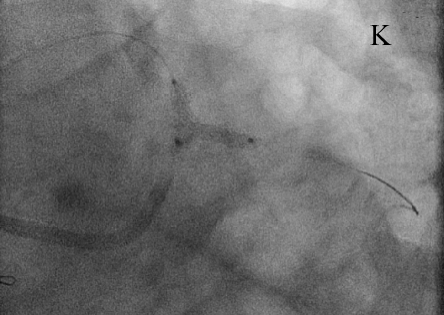

В устье ОВ с переходом на ее проксимальный сегмент был имплантирован стент XienceV (и), после чего выполнена постдилатация по методике «целующихся» баллонов (к). При контрольной КГ стентированные сегменты проходимы, достигнут хороший ангиографический результат (л).